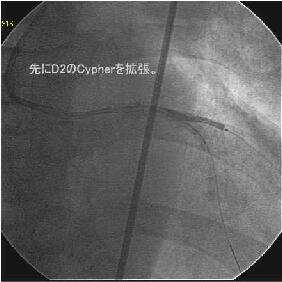

Crush�̎�Z�B